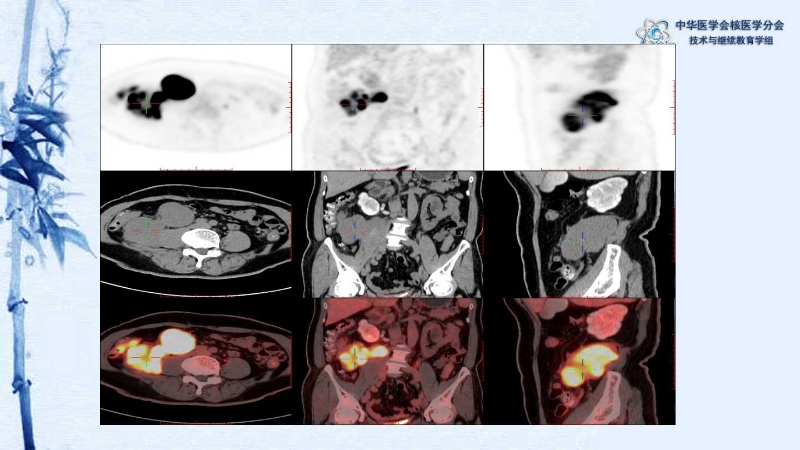

【CSNM继教学组】病例E51-邢岩-结肠炎性肌纤维母细胞瘤18F-FDG PET/CT显像